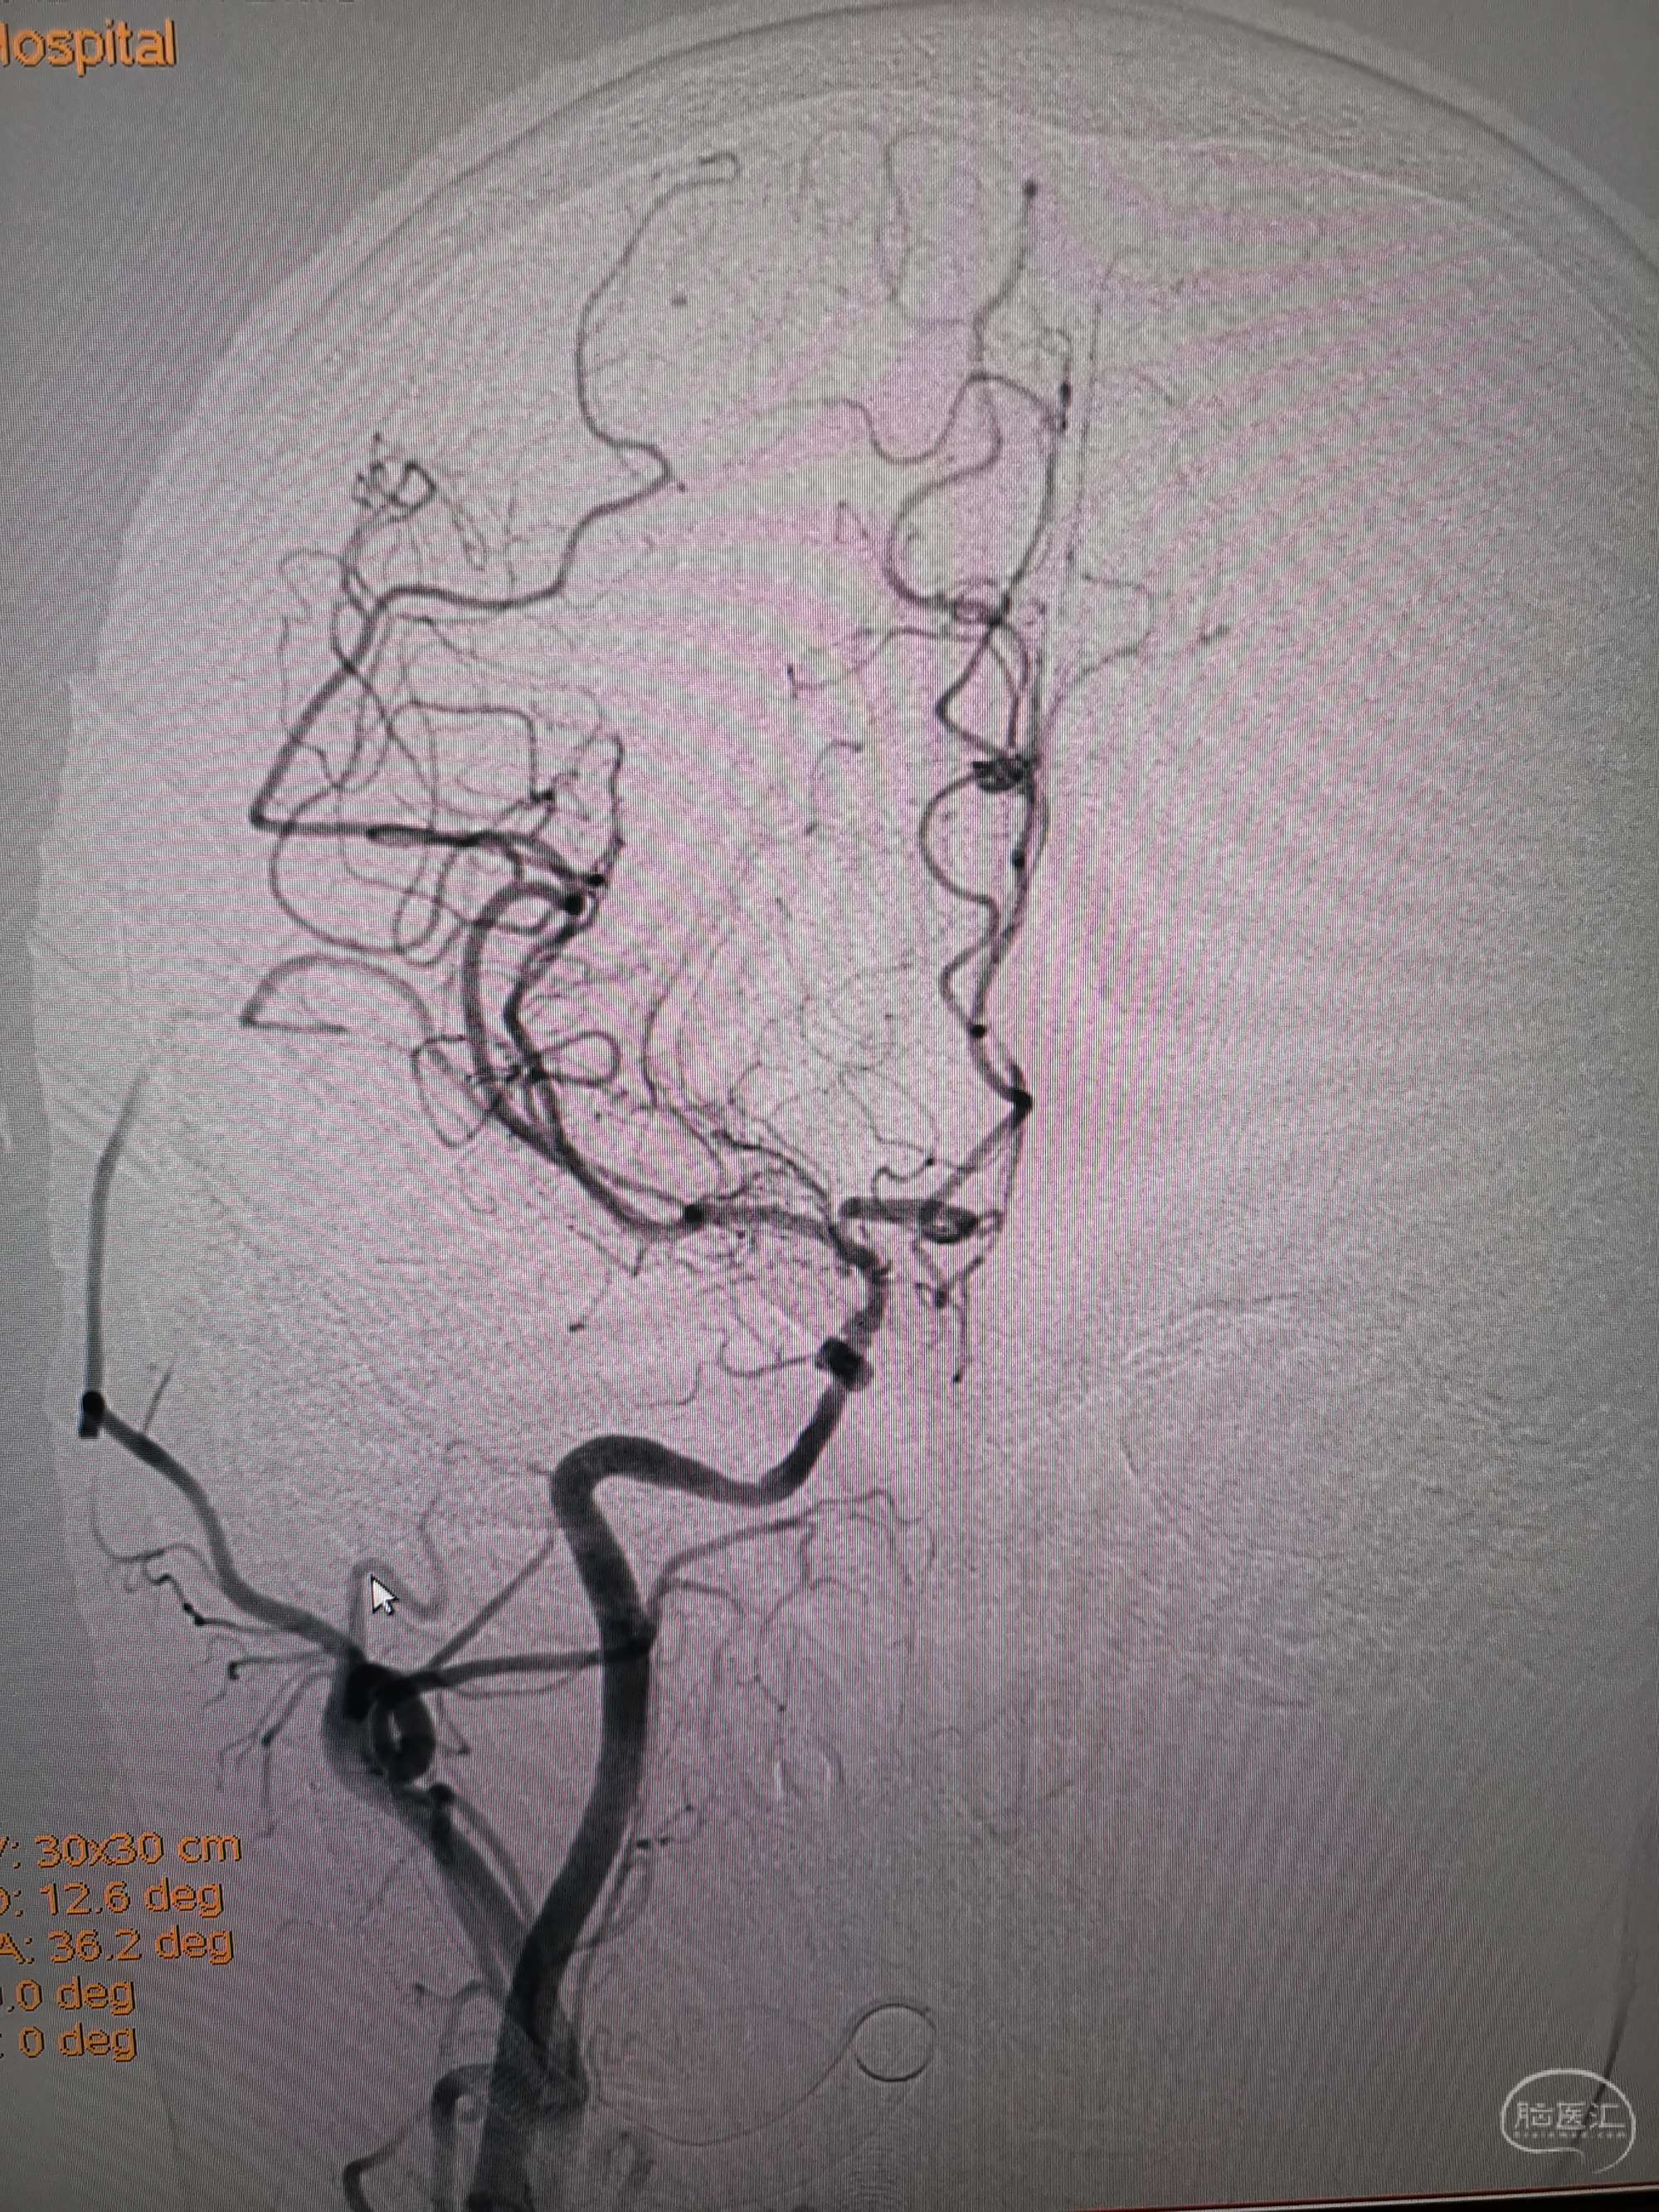

术前再次造影评估

右侧椎动脉穿支供血及左侧PICA供血较入院时略有改善,但改善不明显。故按计划行左侧椎动脉再通术

手术过程

在微导管支撑下先将微导丝和微导管穿过闭塞段,微导管超选造影证实位于基底动脉真腔后更换300cm外周交换导丝,撤出微导管后按从小到大,从远到近的原则行球囊扩张,本例手术选择了1.5✖️15、2.0✖️20、2.5✖️20球囊进行扩张,扩张满意后植入Enterprise支架,手术结束。